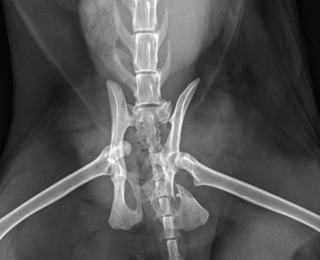

Pelvic trauma is a common finding in feline blunt-trauma patients and survey radiographs are recommended, even in ambulatory cats (Figure 9). Crepitus on manipulation of the pelvic limbs or palpation of fractures directly via rectal examination can provide an initial indication. Sacroiliac, coxofemoral and distal joint luxations, as well as long bone fractures are also fairly common and may be evident on physical examination or can be assessed on survey radiographs. The abdomen should also be carefully palpated for subtler abdominal wall ruptures (Figure 10).